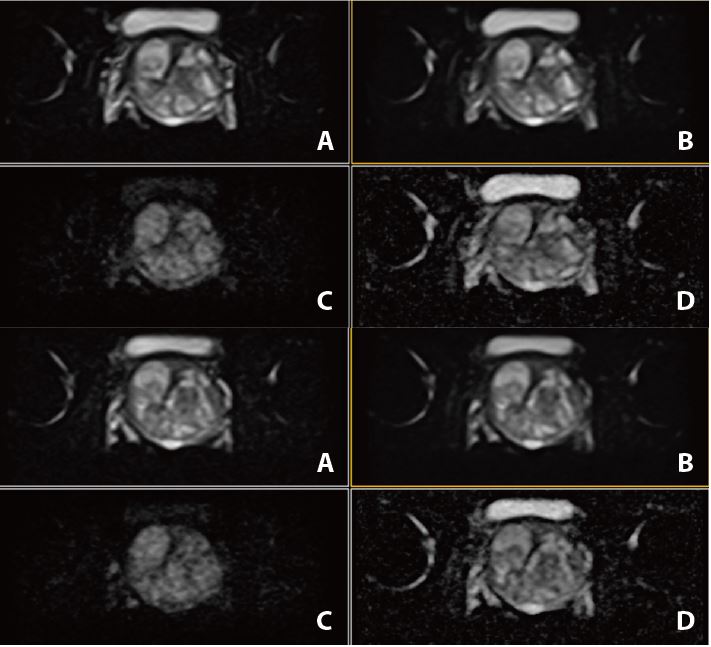

Рис. 3. Аксиальне DWI – A=b0, B=Iso b800, C=Iso b1000 e, D=Iso ADC (за протоколом mpMR)

Рис. 7. Аксіальне DWI – A=b0, B=Iso b800, C=Iso b1000 e, D=Iso ADC (за протоколом mpMR)

Рис. 11. Аксіальне DWI – A=b0, B=Iso b800, C=Iso b1000 e, D=Iso ADC (за протоколом mpMR).

Рис. 15. Aксіальне DWI – A=b0, B=Iso b800, C=Iso b1000 e, D=Iso ADC (за протоколом mpMR)